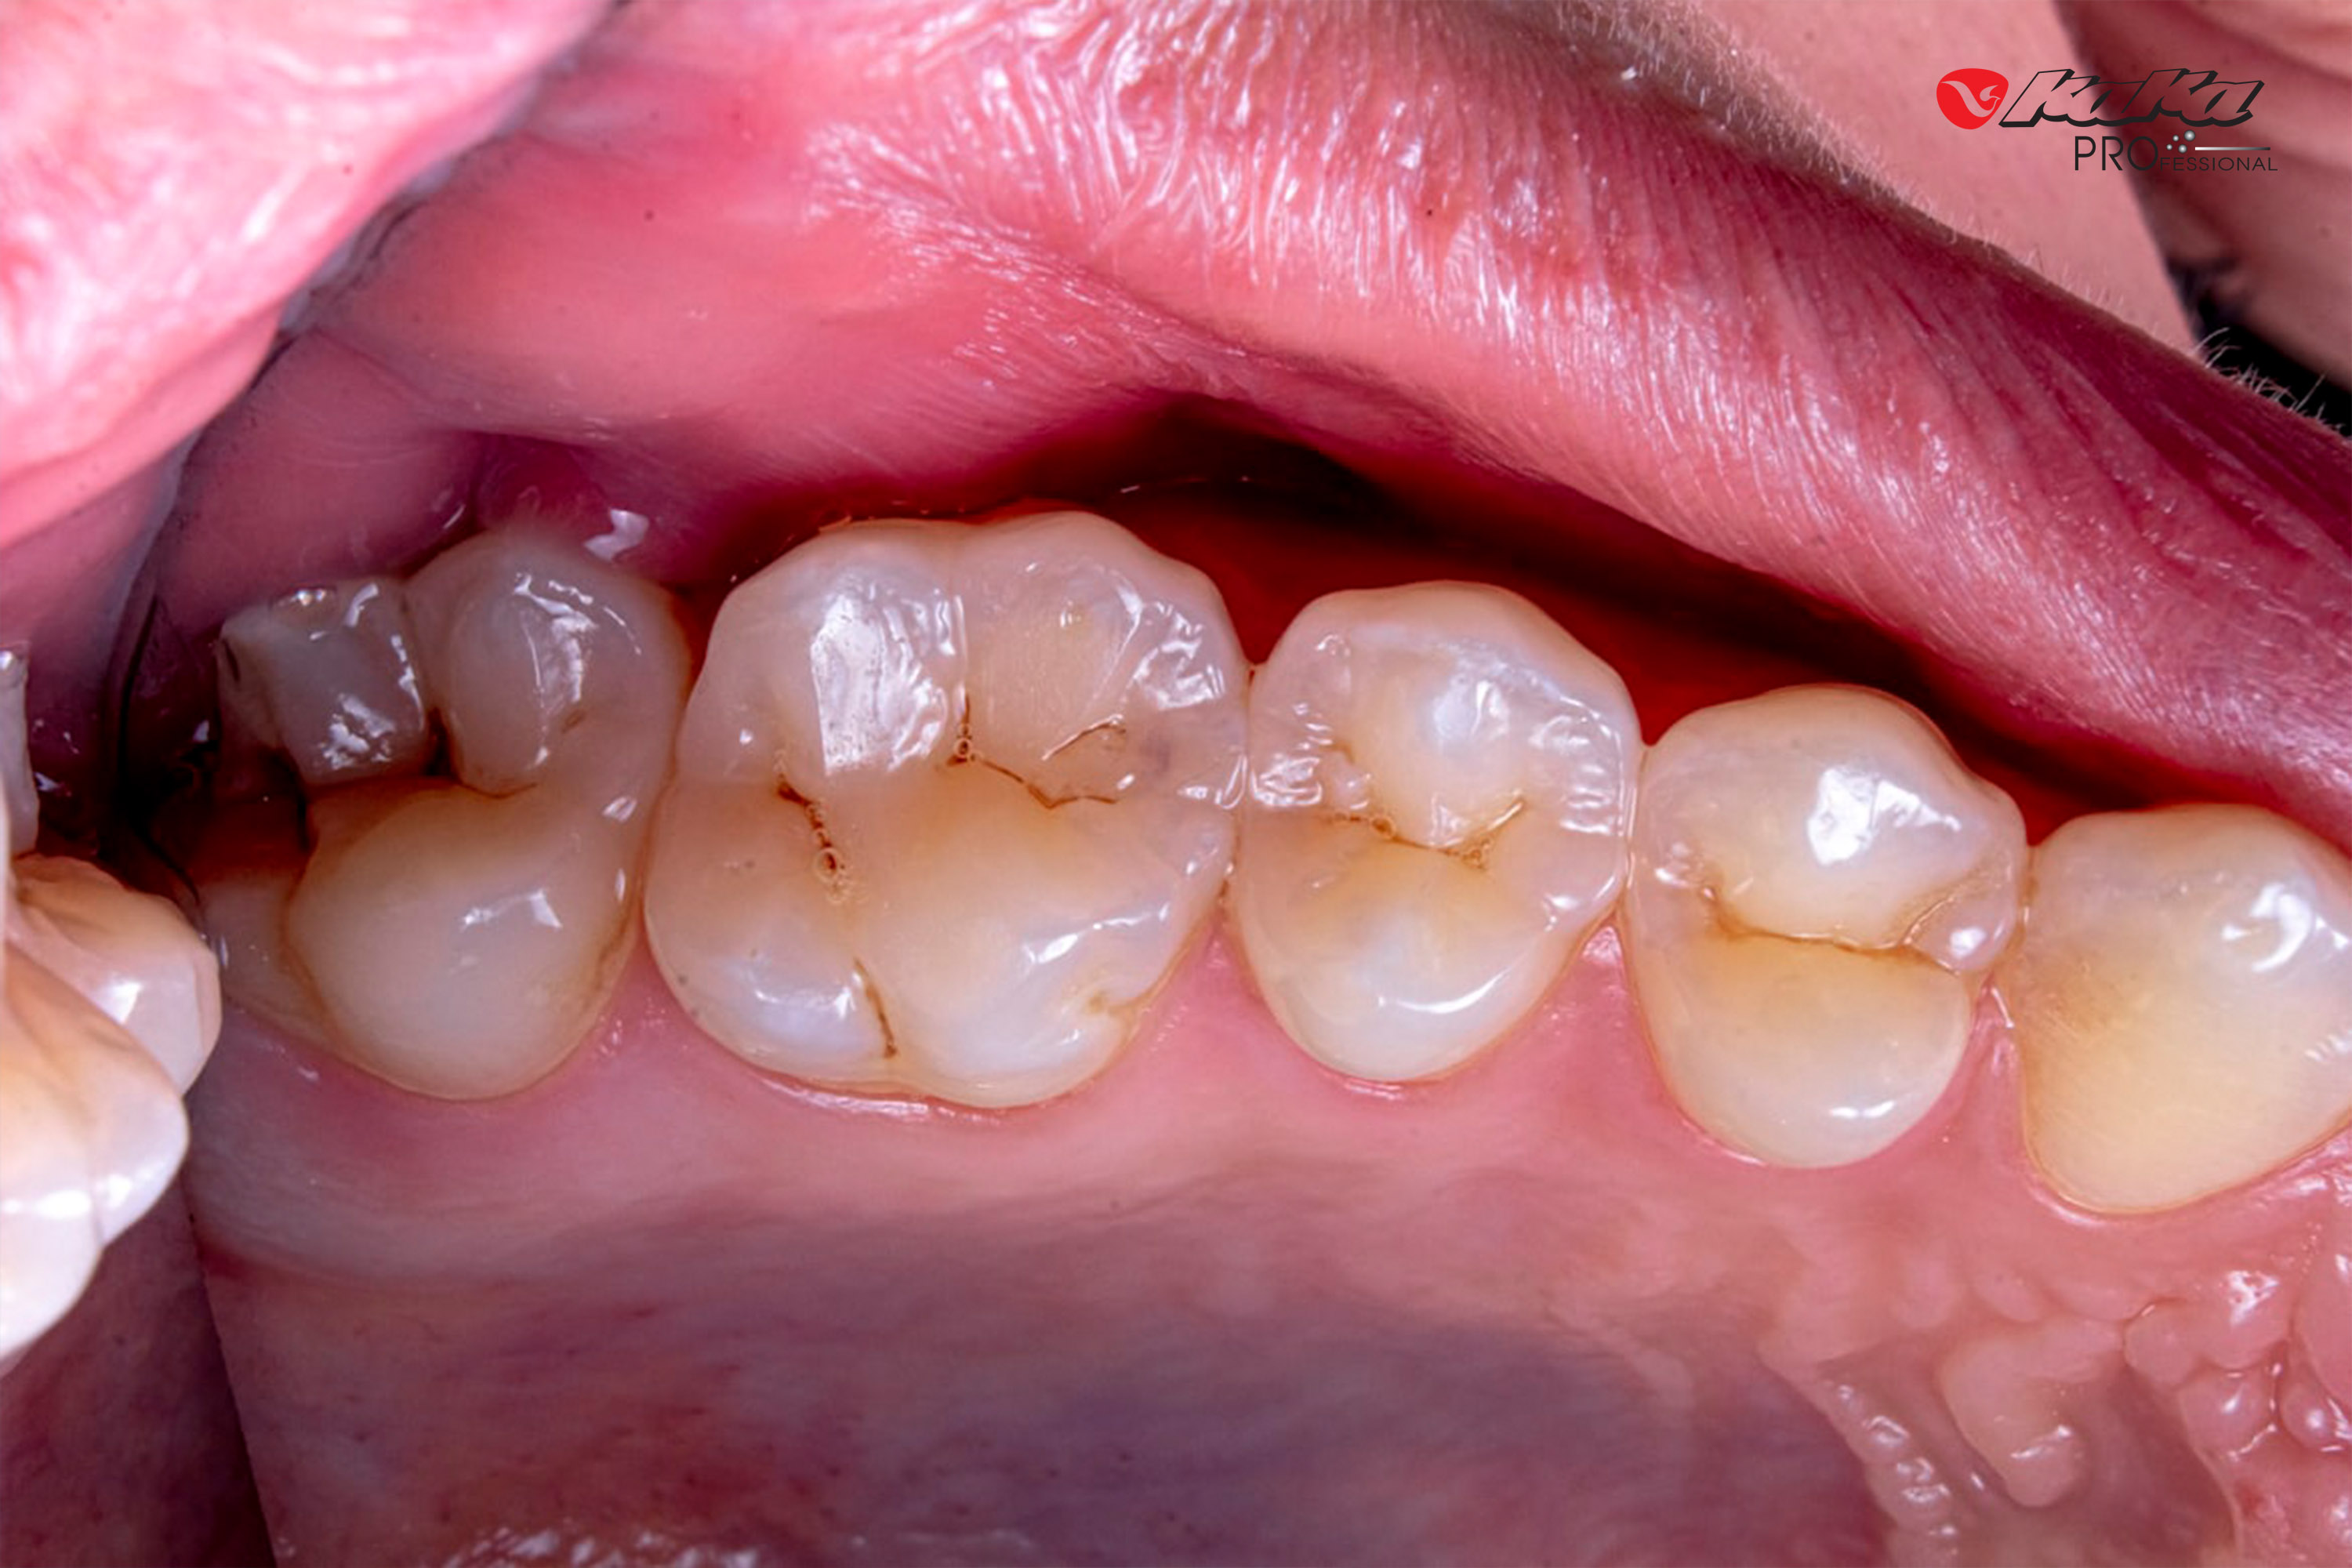

Xuất hiện các lỗ sâu nhỏ: Men răng yếu tạo điều kiện cho vi khuẩn hình thành các lỗ sâu, ban đầu có thể là những đốm trắng đục hoặc đen nhỏ.

Xuất hiện các lỗ sâu cũng là một dấu hiệu của mòn men răng